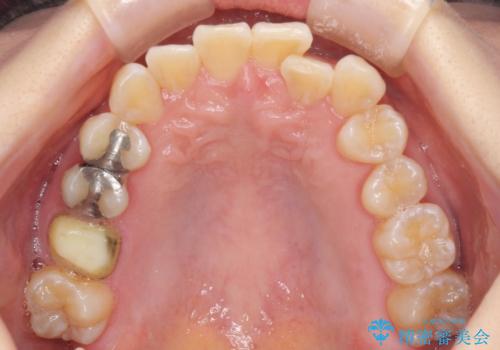

前歯のクロスバイト インビザライン矯正で改善

- むし歯治療を契機に、長年気にしていた前歯のクロスバイトの改善を希望された患者様です。

汚れが溜まりやすく、歯ぎしりがうまくできないため、インビザラインを用いて矯正治療を行うこととしました。

インビザラインによる前歯のクロスバイトの改善は、治療期間中に前歯でしか咬めない時期が続いたり、歯肉退縮や歯髄壊死のリスクが高まったりと、治療中にトラブルを抱えることがあります。

特に上顎側切歯(真ん中から2番目の歯)が舌側に引っ込んでいるケースは、インビザラインでは改善しきれないことがあると言われています。